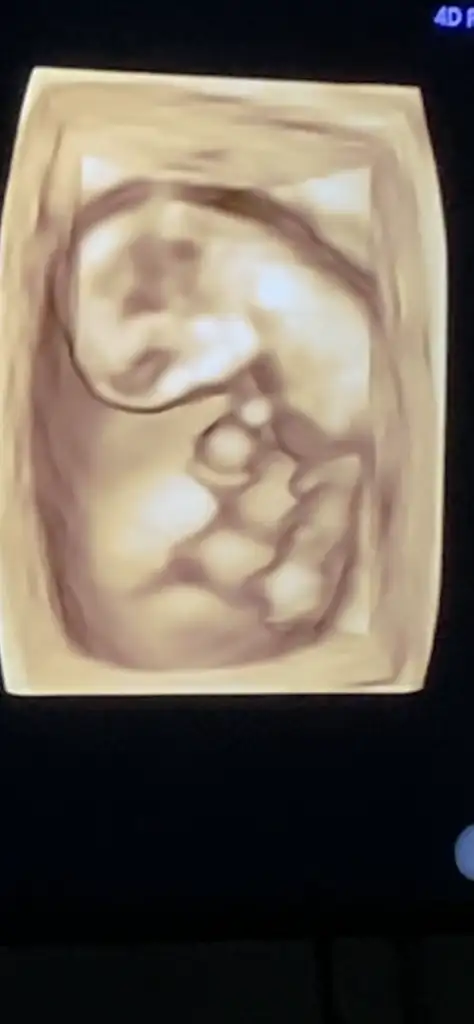

Hani kız pipiKızlar merhaba doktorumu değiştirme kararı aldım ikili testimi devlette yaptırmıştım sonucunu göstermek istedim tersledi beni kibarca kovulduk gibi oldubakmayın gülüyorum ama çok içerlendim yani çalıştığım hastanenin imkanlarımı kullanmam çok mu saçma anlamadım. Eşim çok sinirlendi paranız mı yok gibi bir muhabbet döndü. Bilmiyorum inşallah içime sinen bir doktor bulabilirim %80 erkek dedi bakın bu da üç boyutlu halimiz galiba pipimiz gözüküyor çok hareketliymiş

Şu bacak arasındaki pipi değil mi yahuHani kız pipi

Galiba orası ben hareketli olarak izleyince daha iyi anlaşılıyorAyy şu mu yoksa

Evet bizde bakıp gülüyoruzAy ben gördüm pipiyi çok komik sağlıkla gelsin inşallah